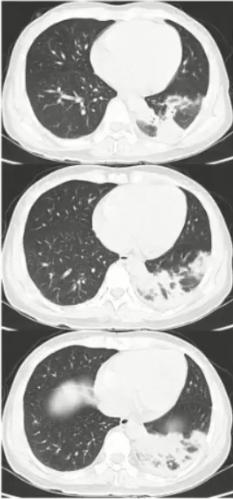

图4 患者肺部CT表现

图5 影像学表现为实变